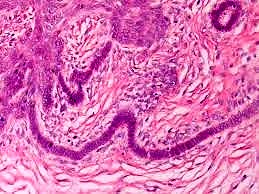

Bazal hücreli karsinom tanı ve tedavisi

Bazal hücreli karsinom; Kıl follikülünden köken aldığı düşünülen derinin malign bir tümörüdür. Bazal hücreli karsinomun tanısı, belirtileri, tedavisi...